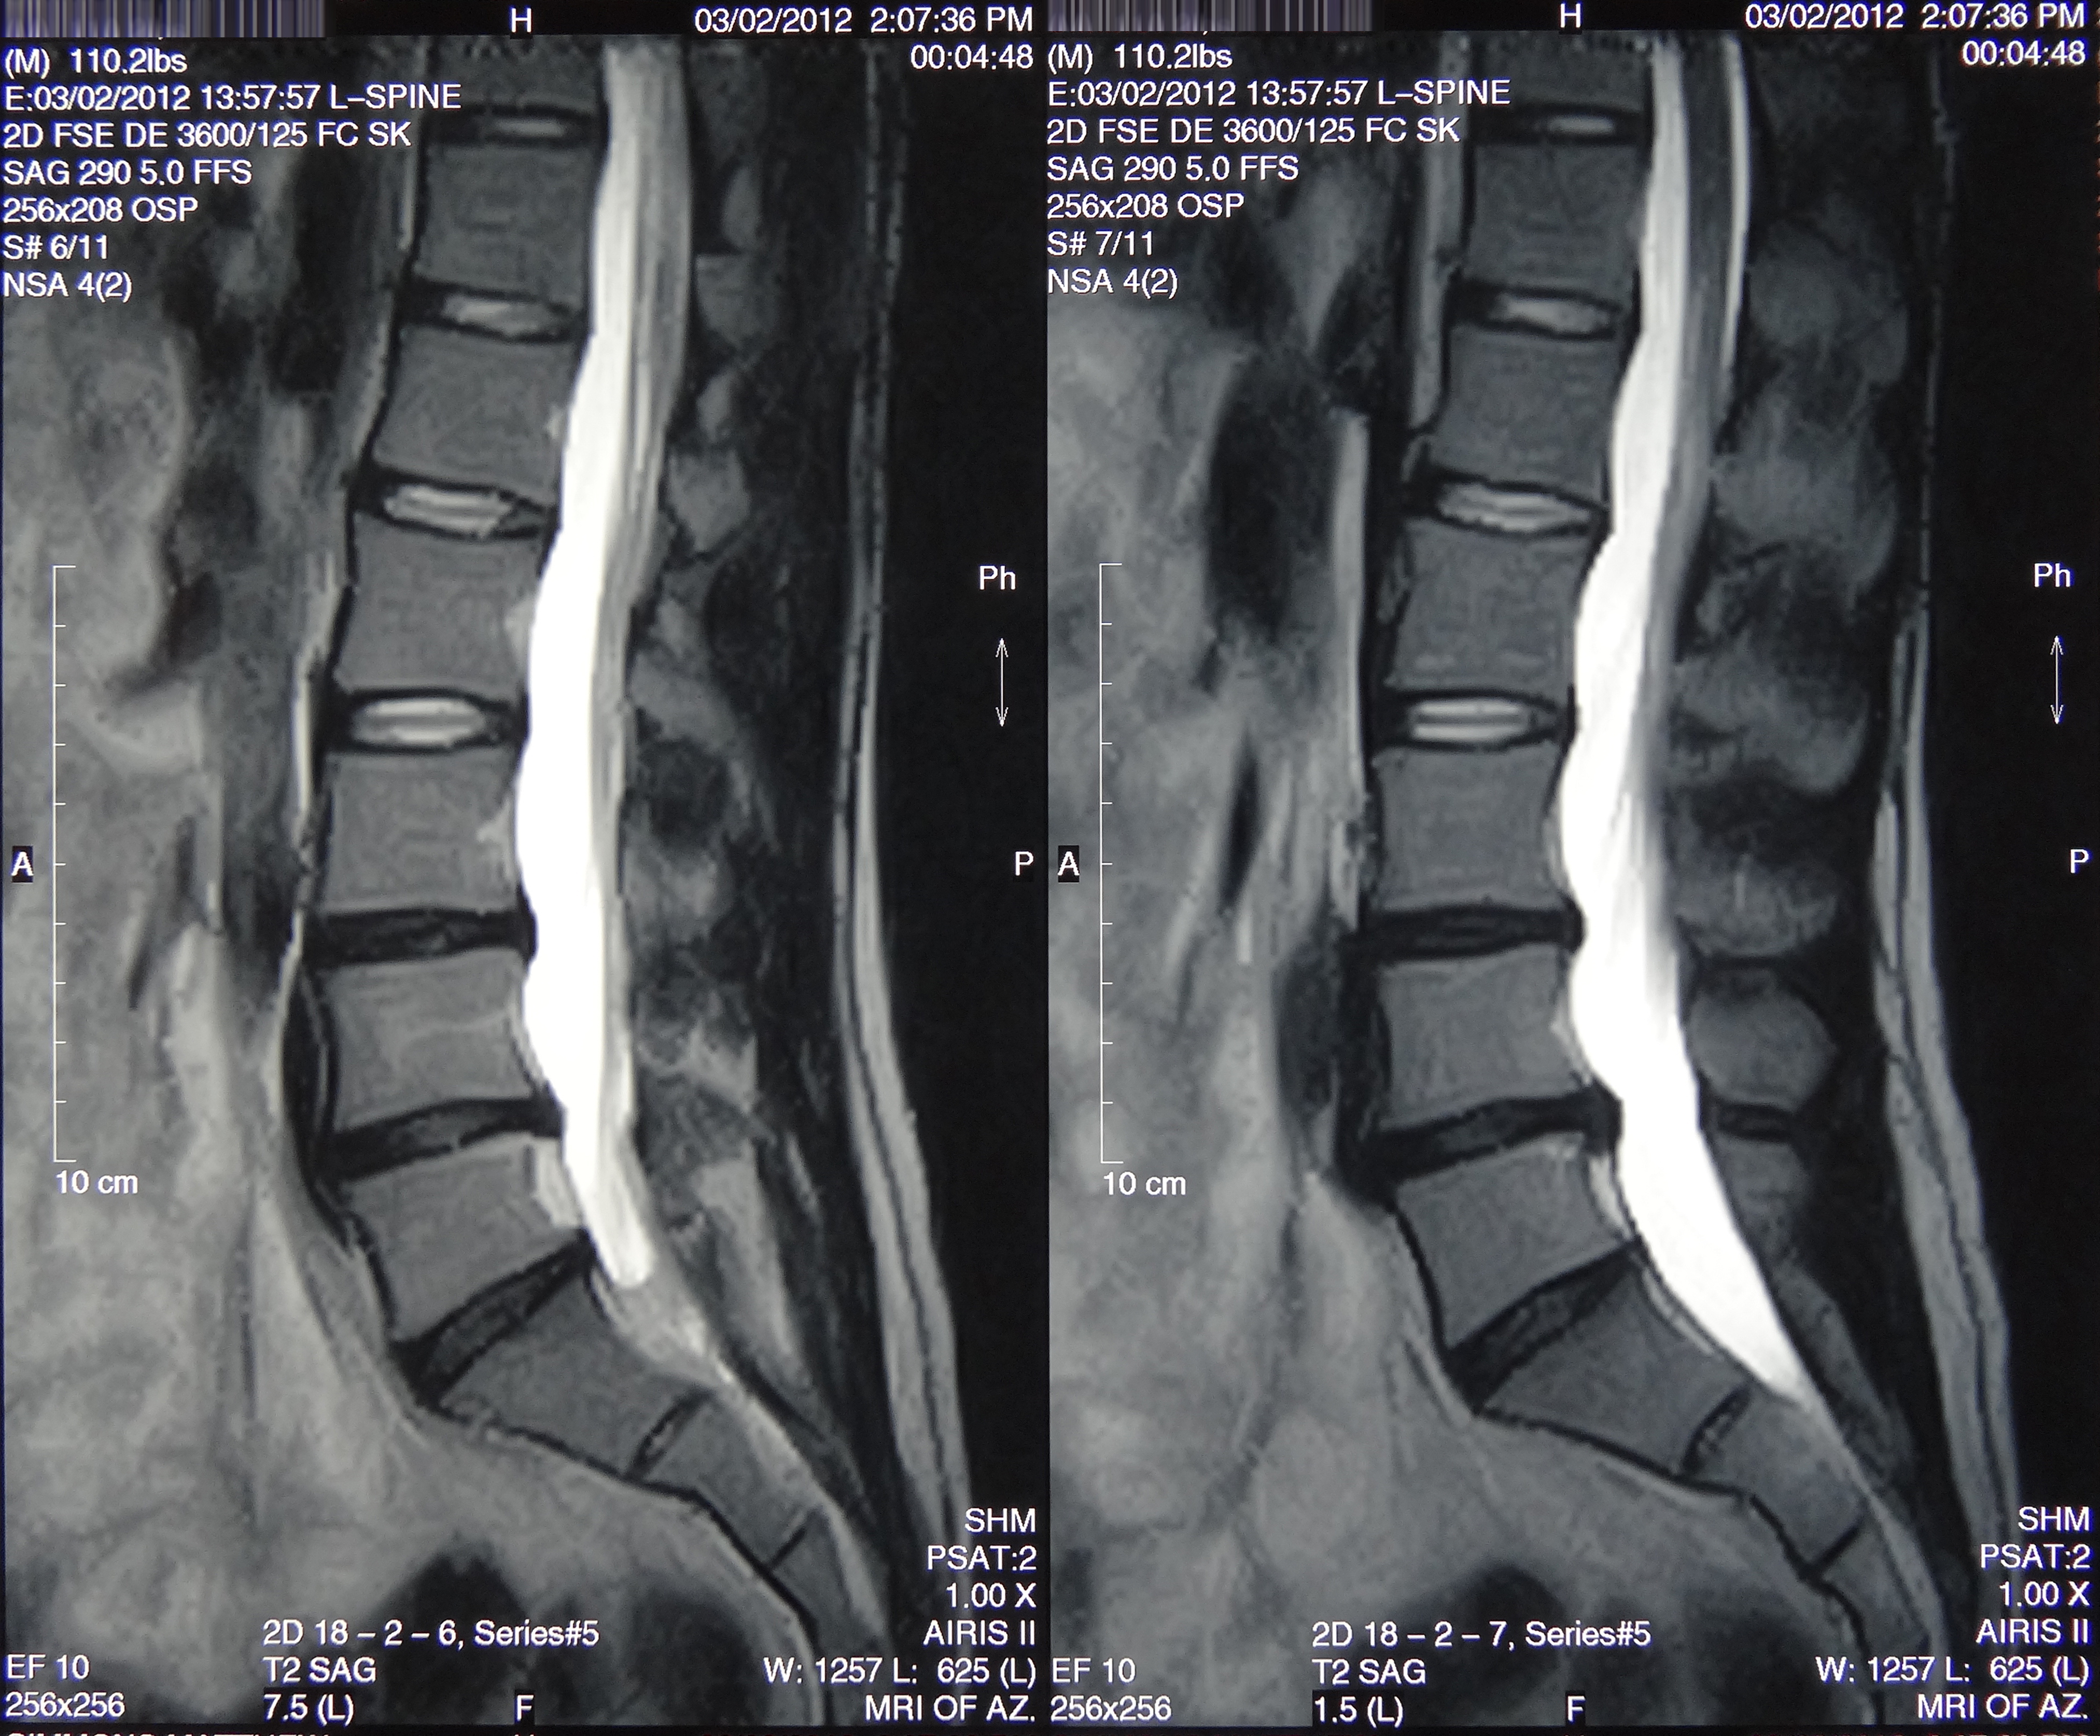

March 2019 MRI

IMPRESSION:

- Complete rupture proximal third anterior cruciate ligament with pivot shift

pattern of bone injuries lateral compartment and contrecoup bone contusion

medial tibial plateau. Joint hemarthrosis. - Complex tear lateral meniscus with inferiorly flipped flap tear extending

into the popliteal hiatus. - Complex tear medial meniscus with outwardly extruded tears of the posterior

horn and body. - Low-grade sprains medial collateral ligament and medial posterior oblique

ligament. - Low-grade sprains fibular collateral ligament and anterolateral ligament.

Intermediate to high-grade sprain popliteofibular ligament and arcuate ligament. - Grade 1 strains vastus lateralis, short head biceps, sartorius, soleus,

popliteus and anterior compartment muscles.